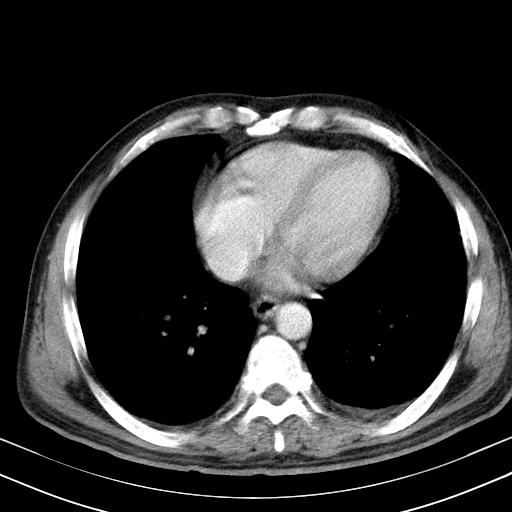

先行ct平扫,纵膈内多发软组织影,ct值约为36hu,以下为增强扫描和腹部平扫。

经典?纵膈多发肿大淋巴结。腹膜后未见异常。

还见胃窦壁增厚!转移亦有可能!

1)考虑淋巴瘤。2)双侧少量胸腔积液。